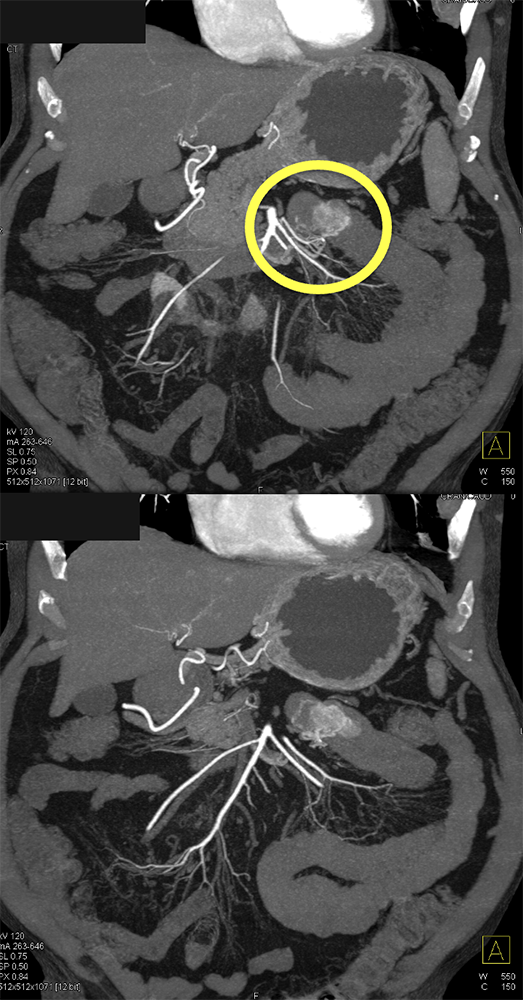

GI Bleed ![]() |

![]() |

GIST Tumor Duodenum ![]() |